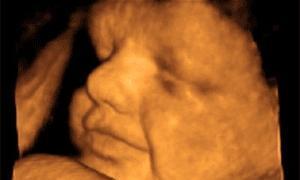

La plataforma Ginecólogos por el Derecho a Vivir (Ginecólogos DAV) ha entregado a la ministra de Sanidad, Trinidad Jiménez, un vídeo con ecografías en dos y tres dimensiones de fetos de doce semanas de gestación , así como una copia del Código de Ética ... y Deontología Médica.